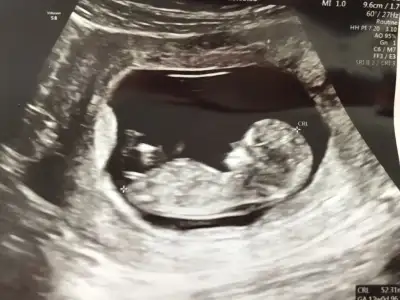

11. Haftamdayım tahmin yapar mısınız?